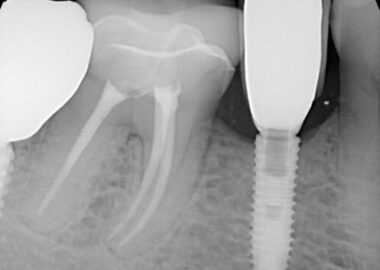

The patient presented on referral from Dr. Z. for retrieval of a fractured abutment screw fragment from a DIO 3.0 implant in the #29 site. By history from the patient, the implant restorative was in for approximately 6 weeks when the screw fractured. Evidently, he had returned to the office with a tight contact issue, but the timing is unclear. When he returned with the loose crown the fractured abutment screw was discovered and he was referred here. There were no previous attempts made at recovery. After discussing the treatment protocols for recovering screw fragments, the area was infiltrated, and a conservative exposure of the implant top was made taking care to spare the thin attached tissue on the facial side. Under the clinical microscope at 25x, the screw fragment was found to be mobile but located just below the implant first thread. This is a Type III case in my treatment algorithm. The fragment was carefully rotated clear of the implant threads and retrieved. The implant was cleaned and in the absence of an appropriate healing abutment a small drop of silicone impression material was placed to act as a temporary healing abutment until the appropriate healing abutment could be installed by his restorative dentist, Dr. Z. The implant was totally intact and the prognosis for the site is unchanged secondary to the screw fracture or the recovery.

The third reason for failure mentioned above relates to the size of the implant and connection in general. This is a 3.0mm implant which is a copy of the Astra Tech 3.0 Tx implant in all of the critical design features and dimensions. Astra has an FDA clearance for their implant to be used in maxillary laterals and mandibular incisors only. I don’t know if the same holds true for this DIO copy, but I would assume so. Why is this an issue in a small diameter implant? A 3.0 two-piece implant can only be made to withstand a certain amount of force. A posterior application will generate significantly greater force on the implant pillar than in an anterior application, hence the FDA ruling. This additional load stresses the connection and the force will be magnified more by torsional loading (force x leverage arm). In the following photograph it can be seen the restoration has a buccal cantilever due to lingual implant position.